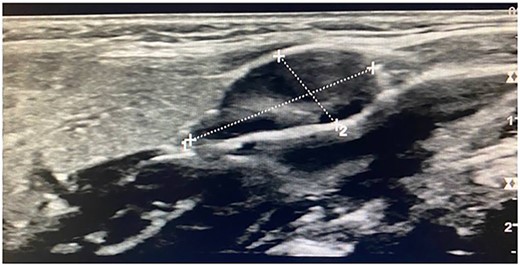

Imaging examination of the patient was done by performing CT and US. US Doppler showed a right dilated internal jugular vein (Fig. 2). The CT scan confirmed this finding, which suggested internal jugular vein phlebectasia (Fig. 3).